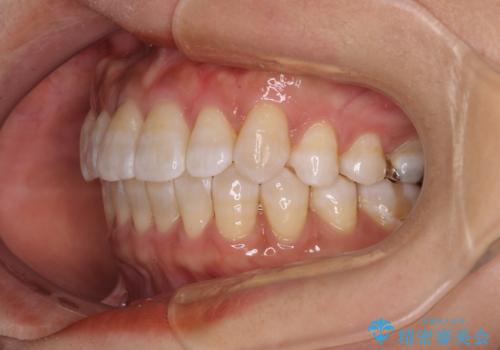

気になる八重歯 ワイヤー装置での非抜歯矯正

口元の突出感はなかったため非抜歯矯正での対応となりますが、八重歯を改善する際に上顎前歯が前突する可能性があったため、上顎臼歯部にアンカースクリューを使用して、歯列が前方に転位しないようにすることとしました。

また舌のトレーニングを行うことで、上顎前歯の突出予防や上下前歯に隙間ができなくなるようにしました。

ワイヤー矯正でもインビザラインでも対応可能でしたが、上顎歯列が前方位であるときには、ワイヤー矯正の方がより良い仕上がりとなる可能性が高いため、ワイヤー矯正をおすすめいたしました。